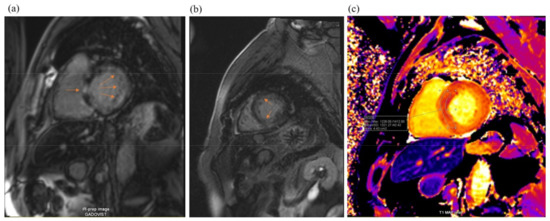

Cardiac magnetic resonance imaging (MRI) (Figure 4) found signs of infiltrative myocardial damage. The LV volumes were not dilated, with an interventricular septum thickened up to 20 mm and a maintained LVEF of 67%. Native T1 values were elevated to 1321 ms. LGE analysis showed a linear and focal diffuse delayed accumulation of gadolinium, with prevalent subendocardial late gadolinium enhancement (LGE) accumulation in the basal and middle LV segments.

Figure 4.

Cardiac magnetic resonance imaging: LV hypertrophy with diffuse subendocardial late gadolinium enhancement (arrowheads, pictures (a,b)) and some zones of focal late gadolinium enhancement (arrow, picture (c)). T1 mapping shows markedly increased values (1321 ms).